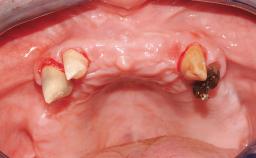

A 68-year-old, completely edentulous male patient presented for evaluation and treatment options. He reported excellent general health and was taking no regular medication. He had been edentulous for approximately 12 years, having lost his teeth to periodontal disease and dental caries. The patient’s chief complaint was incompetent function. His secondary concerns included his appearance and the desire for a predictable outcome. He attributed his reduced functional capacity to his lower complete denture, which he described as poor. He was particularly concerned with the denture’s instability and poor fit. In general terms, he was satisfied with the maxillary complete prosthesis. The maxillary prosthesis was characterized by adequate retention, stability, and support, although the fit was considered less than ideal.

Case Type Edentulous Mandible

Jaw Mandible

Area Full-Arch

# of Teeth All